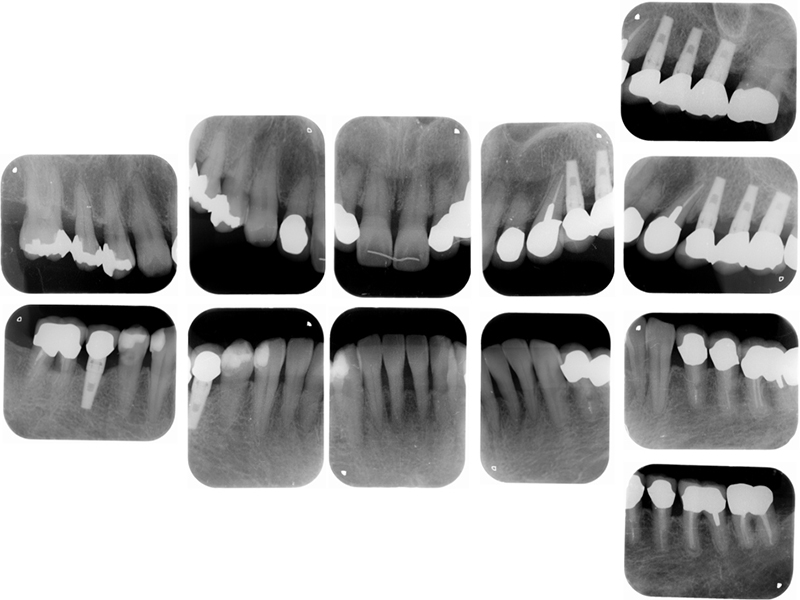

▼ ケース5 下顎前歯部叢生症例

初診時口腔内写真

初診時X線写真

治療終了時

before

after